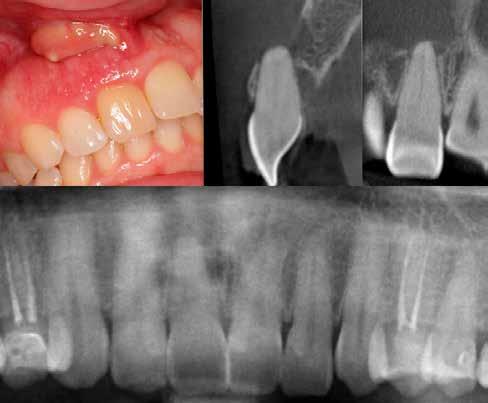

Krell és Caplan kutatásában 2086 repedt fogat vizsgáltak meg. A vizsgált fogak között leggyakrabban a második alsó nagyőrlőfogak (36%), majd ezt követően az első alsó nagyőrlők (27%), és végül az első felső nagyőrlők (18%) fordultak elő. A kutatási eredményeik szerint a fogbél állapota nem befolyásolta jelentős mértékben a kezelés várható kimenetelét. (Irreverzibilis pulpitis 85%; necrosis 80%; korábban gyökérkezelt 74%). A kimenetel szempontjából ugyanígy indifferens volt a páciensek neme, életkora, a kezelés időpontja, a fog pozíciója, a fog helyreállítása során használt anyag típusa, valamint az érintett fogfelszínek száma. 2014 júliusában egy 45 éves hölgy páciens azzal a panasszal kereste fel a rendelőnket, hogy nagyjából 10 napja egy fájdalmas duzzanat alakult ki a jobb felső első kisőrlője koronája mellett (14). A klinikai vizsgálat során egy amalgámtömést találtunk a panaszos fogban. A tömés széli zárása nem volt megfelelő, a disztális záróléc és a tömés között rést tapasztaltunk. A fog disztobukkális és linguális felszíne mellett 8 mm-es csontos tasakokat mértünk. A periapikális felvételen az 14-es foggyökér disztális felszínének megfelelően vertikális irányú radiolucens felritkulást észleltünk. A klinikai vizsgálat során a mesiális zárólécet kettéválasztó törésvonalat detektáltunk (17–18. ábra). A fogszenzibilitás vizsgálata során negatív eredményt kaptunk. A páciensnek ismertettük az elérhető terápiás lehetőségeket: 1, a 14-es fog eltávolítása, majd a foghiány 3 tagú cementezett híddal történő pótlása; 2, a 14-es fog eltávolítása, kemény- és lágyszöveti augmentáció, majd implantátum behelyezése; 3, a 14-es fog gyökérkezelése, gyökértömése és ezt követően a csücsökborítást biztosító restaurátum készítése. Arra is felhívtuk a páciens figyelmét, hogy a 3. terápiás lehetőség választása esetén nem tudjuk a fogmegtartás sikerességét garantálni, de végül – főként anyagi okok miatt – mégis ezt a terápiás opciót választotta. Fontos megjegyezni, hogy a repedt fogak ellátási lehetőségeit a törésvonal mélysége, elhelyezkedése, lefutása nagyban befolyásolja. A kezelés megtervezése során a fog és a fogat körülvevő szövetek állapotával kapcsolatos számtalan különböző faktort kell egyidejűleg figyelembe vennünk. A gyökérkezelést követően a gyökértömést meleg vertikális kondenzációs technikai alkalmazásával készítettük el (19. ábra). A hozzáférési nyílást folyékony és hibrid kompozit tömőanyag segítségével zártuk. A zárás elkészítése során a dr. David Clark által kifejlesztett Bioclear matricarendszert alkalmaztuk. A 6 éves kontroll során készített (2020) röntgenfelvételen a csontos defektus telődése volt megfigyelhető. Ez is a parodontális defektus gyógyulását igazolta (20–21. ábra).

17. ábra: A 14-es fog gyökerének disztális felszíne mellett vertikális csontpusztulásra utaló jelek észlelhetőek. Klinikailag ezen a területen 8 mm mélységű tasakmélységet mértünk. – 18. ábra: A 14-es fog disztális zárólécének megfelelően törésvonal észlelhető, ugyanakkor a csücskök teljes szeparálódására utaló jelek nem láthatóak. Az amalgámtömés eltávolítását követően jól megfigyelhető volt a törésvonal teljes lefutása. – 19. ábra: A gyökértömés elkészítése során meleg vertikális kondenzációs technikát alkalmaztunk. A felvételeken oldalcsatornák jelenlétére utaló jelek is észlelhetőek. – 20–21. ábra: A 2020-ban készült kontrollfelvételeken jól látható a csontos defektus telődése. A radiológiai jelek alapján (jól lekövethető gyökérhártyarés) a parodontális ligamentumok regenerációját is vélelmezzük.